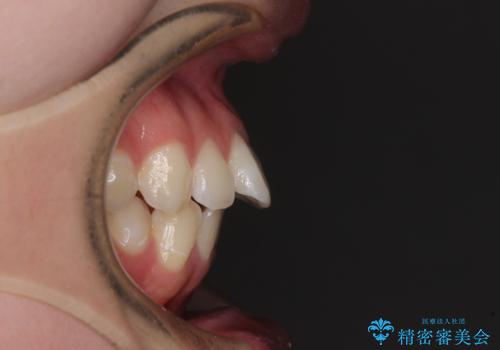

- 飛び出した上の前歯やデコボコを気にして来院された患者様です。

上下前歯の突出感とデコボコを気にして来院された患者様です。

インビザラインによる上下歯列の側方拡大と後方移動、必要に応じてIPR(歯と歯の間を削る)によりスペースの獲得により歯列を整えることとしました。